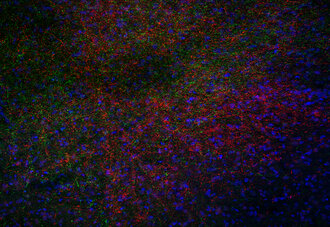

Indirect immunostaining of a rat brain (BNST) section for CRF (red) and Neuropeptide Y (green)